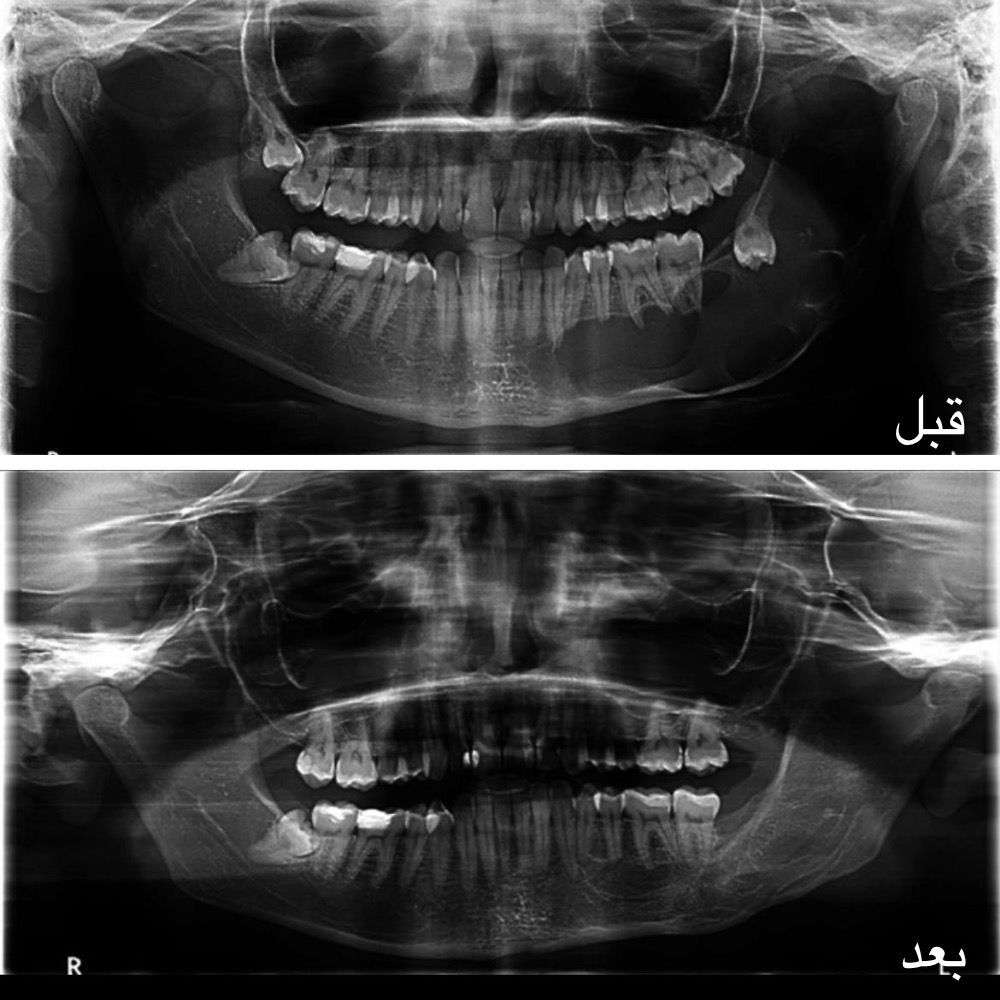

مدينة الملك سعود الطبية تحقق إنجازًا طبيًّا عالميًّا بتقنية مبتكرة لعلاج الأورام الكيراتينية الفكية

الاحساء – زهير بن جمعه الغزال حقّق قسم جراحة الفم والوجه والفكين بمدينة الملك سعود